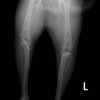

■ 症例22 ポメラニアン 1歳5か月 去勢雄

左後肢の挙上を主訴に来院した。整形学的検査、レントゲン検査より左右の膝蓋骨脱臼(左GradeⅡ〜Ⅲ、右Grade Ⅱ)を認めた。また、脛骨の前方引き出し試験の際に、引き出し兆候は認められないものの、疼痛が認められたため、前十字靭帯の損傷が疑われた。術中における、目視および関節内の操作によって、前十字靭帯の損傷や過伸展といった異常が認められなかったため、膝蓋骨脱臼の整復のみ実施した。手術手技は縫工筋及び内側広筋の解放、脛骨粗面の外側転位、滑車ブロック形造溝術、内外側関節包の縫縮を実施した。本症例は跛行もなく経過良好である。しかし、頸骨高平部の角度(TPA)が 右26.2°、左24.9°であり、解剖学的に前十字靭帯損傷のリスクが高いことから今後の経過に注意が必要である。